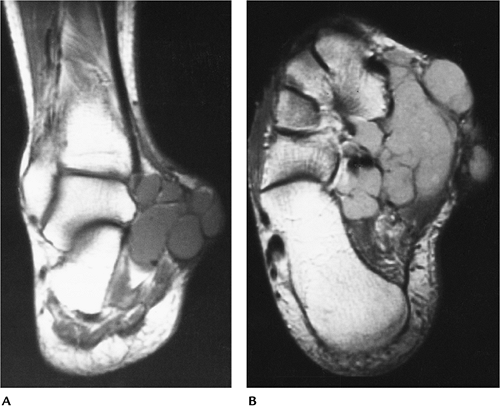

![]() |

FIGURE 6-69 Peroneal tendon ganglion cyst. (A) Radiograph showing focal lateral swelling (arrows). Coronal T2-weighted (B) and axial T1-weighted (C) images showing a homogenous low-intensity lesion on T1-weighted image (C) and high-intensity lesion on T2-weighted (B) images.